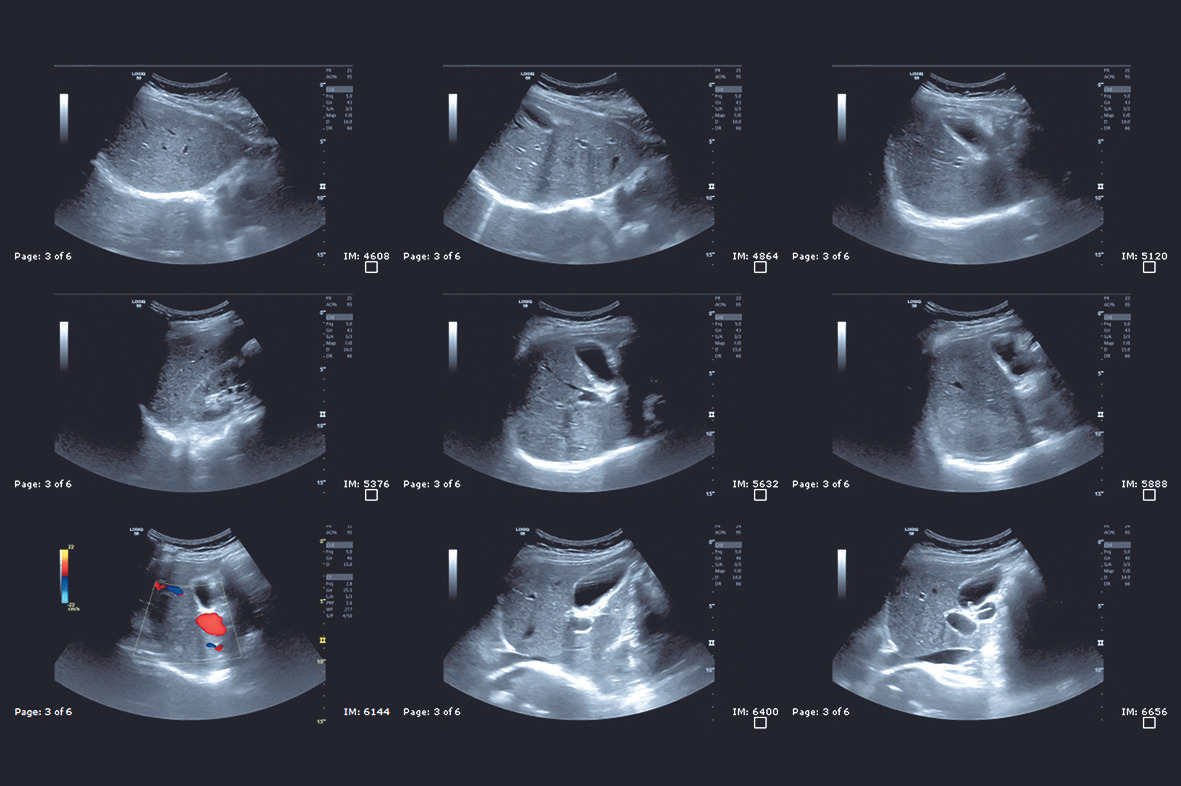

결과 영상을 보면 까만색, 회색, 흰색 영역이 모자이크처럼 보이는데, 이를 통해 장기의 경계, 혹이나 낭종 여부 등을 판별할 수 있습니다. 예를 들어 “신장에 혹과 낭종의 차이”를 진단할 수 있는 것도 초음파로 비교적 쉽게 확인이 가능합니다. 최근에는 해상도가 높은 장비들이 많이 보급되어, 수 밀리미터 단위의 이상도 찾아낼 수 있어 더욱 믿음이 가는 검사죠.

- 신장(콩팥) 부위 초음파는 종괴(혹), 낭종, 결석 등을 점검하기 좋습니다. “신장에 혹과 낭종의 차이”처럼 형태적 구분이 필요할 때 특히 유용합니다. 신장암을 의심해야 할 때도 초음파가 1차적으로 활용됩니다.

- 간 초음파로 알 수 있는 것: 간염, 지방간, 간경변, 간암 등 간의 전반적인 상태를 확인합니다. 간의 크기와 모양, 간 표면의 결절 여부 등을 비교적 명확하게 볼 수 있어 간암 초기 징후도 발견할 수 있습니다. “간 초음파로 암검사” 가능하냐고 물으시는 분들이 있는데, 초음파 검사는 간암을 의심해 볼 수 있는 기초적인 단계에서 유용합니다. 하지만 확진을 위해서는 더 정밀한 영상 검사나 혈액 검사(알파태아단백 등)를 병행하기도 하지요.